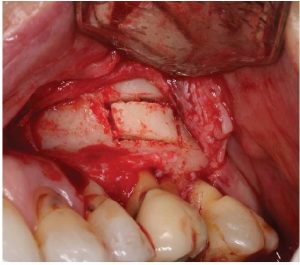

The cervical area of tooth LR3 was severely abraded. An intra -sulcular full-thickness muco-periosteal fap was raised; a vertical re leasing incision was positioned mesial to tooth LRI. The surgical stent was placed over the maxillary teeth (Figure 8) and a piezotome-guided surgical window wasdeveloped using the margins of the stent (Figure 9).

A chisel was used to elevate the cortical plate and root resection performed with Lindemann burs (Figure l0).

The cortical window was placed in sterile saline while the endodontic microsurgery was completed. After resection